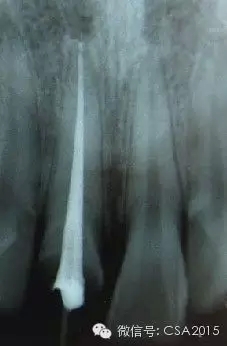

1 術(shù)前拍攝X線片評(píng)估牙齒冠、根情況以及牙槽骨情況

在根管治療過(guò)程中,在根管治療術(shù)前拍X線片,以幫助診斷,了解髓室的位置和根管數(shù)目及形態(tài),測(cè)量根管工作長(zhǎng)度及日后隨訪和評(píng)價(jià)療效提供對(duì)比的依據(jù)。